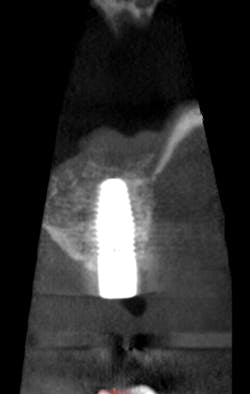

After reviewing the image, we performed a sinus lift procedure and placed two implant fixtures. A follow-up CBCT volume was taken one month later to check for overall healing, graft containment and sinus health (figs. 4, 5). The scan demonstrated normal healing from all perspectives. The patient went on to have the implants successfully restored once integration was clinically confirmed.

Figure 4:

Figure 5: